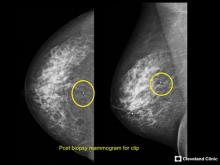

VIDEO: COVID Vaccine May Cause Enlarged Lymph Nodes on Mammograms — Interview with Constance "Connie" Lehman, M.D.

COVID-19 Vaccination Axillary Adenopathy Detected During Breast Imaging